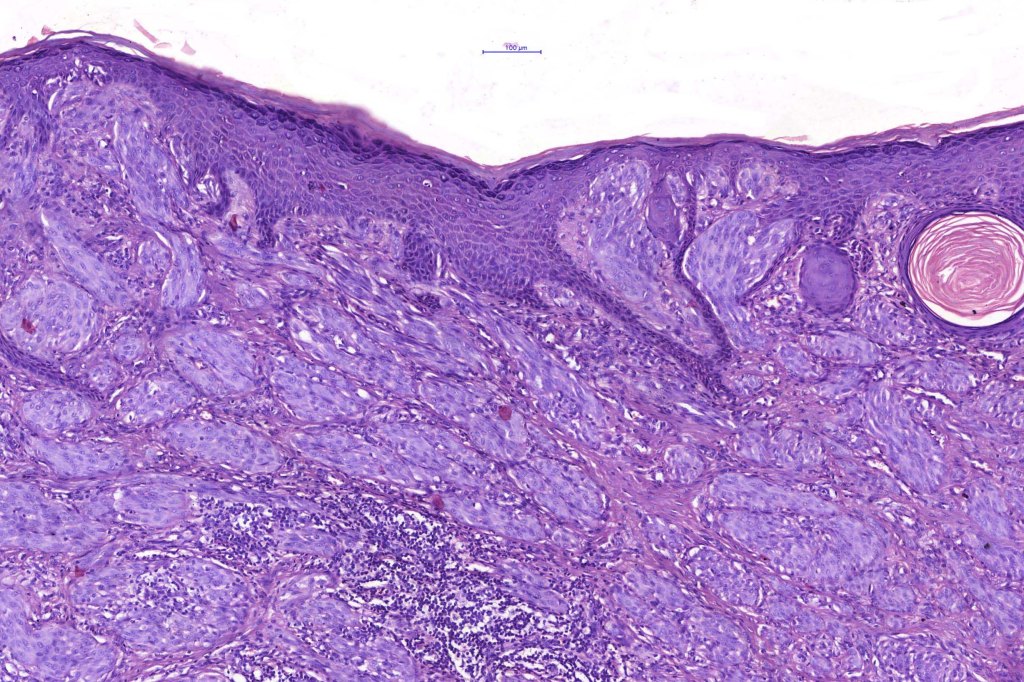

•Sharply circumscribed (begins and ends with a nest), symmetrical dome-shaped lesion. Symmetry is both horizontal and vertical (see image below)

•Wedge-shaped with the base uppermost or sometimes plaque-shaped silhouette

•Matures with depth-often best recognized at scanning/low power magnification & readily confirmed with S100 or MART1

•Maturation implies nest size and cell size diminishing with depth, at the base, the infiltrate may have a single cell infiltrating pattern

•Hyperkeratosis & acanthosis, sometimes very marked

•Kamino bodies (often multiple) are a characteristic feature

•Lymphocytic infiltration at the base of the lesion